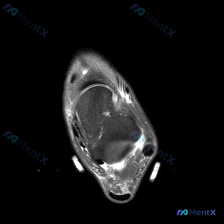

刚看到这份踝关节MRI读片需求,整理了完整的观察和分析思路分享给大家。 病例基本影像信息 本次读片基于踝关节MRI-T2序列轴位图像,扫描层面为踝关节远端轴位,可清晰辨认胫骨、腓骨、距骨以及后方跟腱等正常解剖结构。T2序列对液体和水肿敏感,正常肌腱韧带应为低信号(黑色),液体/水肿为高信号(白色)。...

今天碰到一个有意思的读片矛盾病例,整理出来和大家分享一下思路。 病例基础信息 这是一张踝关节MRI T1加权轴位图像,用户观察到存在软组织液体,但单张影像读片结果如下: 1. 跟骨:骨髓脂肪信号均匀,皮质连续,未见骨质破坏、骨髓水肿或异常占位 2. 肌腱:胫骨后肌腱、趾长屈肌腱、𧿹长屈肌腱、腓骨长短...

刚整理了一份很有代表性的踝关节影像读片病例,分享一下我的分析思路,这个陷阱很多年轻医生都容易踩。 病例基本影像信息 本次仅提供踝关节MRI T1序列轴位图像,核心读片结果如下: 1. 骨性结构:胫骨远端、腓骨远端骨质信号正常,骨皮质完整,未见骨折、骨质破坏,关节面轮廓清晰,无明显骨赘形成 2. 软组...